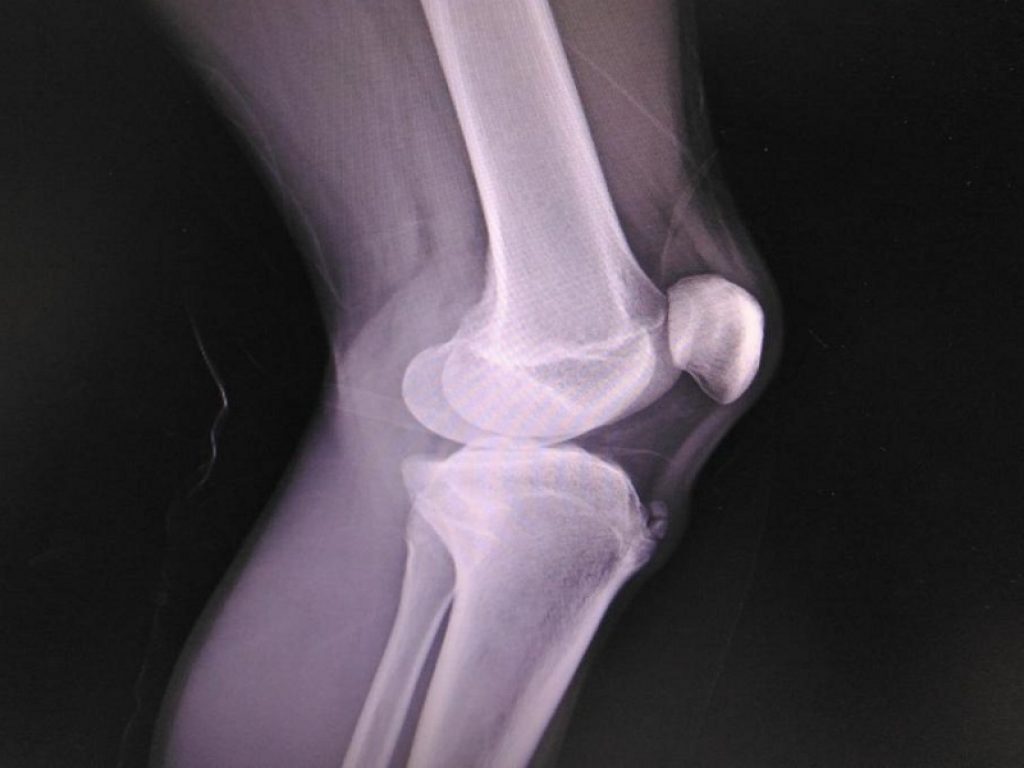

La sindrome di Osgood-Schlatter, un disturbo del ginocchio che colpisce bambini e adolescenti, se non trattato può creare problemi anche da adulti

Un disturbo benigno a carico del ginocchio comune in età pediatrica è la sindrome di Osgood-Schlatter: la tuberosità della tibia, localizzata sotto la rotula, è dolente e gonfia, soprattutto quando si fa sport. L’affezione è associata al processo di accrescimento dei tessuti osseo e cartilagineo e con la crescita tende a scomparire. Ma ci sono ripercussioni da giovani adulti? E se sì, quali? L’abbiamo chiesto al dottor Andrea Bruno, ortopedico e traumatologo di Humanitas.

La sindrome di Osgood-Schlatter è una osteocondrosi che interessa i bambini di età pre-adolescenziale, compresa fra i dieci e i quattordici anni. La prevalenza è maggiore tra i maschi e soprattutto fra chi si dedica all’attività fisica. I movimenti di flessione del ginocchio, basti pensare a quelli eseguiti dai piccoli calciatori, per citare uno degli sport più praticati, possono causare dolore al ginocchio.

«La sindrome interessa l’apofisi tibiale anteriore, ovvero il nucleo di accrescimento della tuberosità tibiale», spiega il dottor Bruno. I sintomi sono la tumefazione e il dolore, spesso a una sola delle due gambe, «senza limitazioni funzionali», ricorda lo specialista. La dolenzia è indotta dalla flessione del tendine che collega il muscolo quadricipite della coscia con la tibia, «ecco perché i sintomi si avvertono durante la pratica sportiva, con la corsa o saltando, ma anche quando si salgono le scale». La sindrome tende ad andare incontro a guarigione spontanea e comunque con la fine del processo di crescita dei tessuti, intorno ai diciotto/diciannove anni.